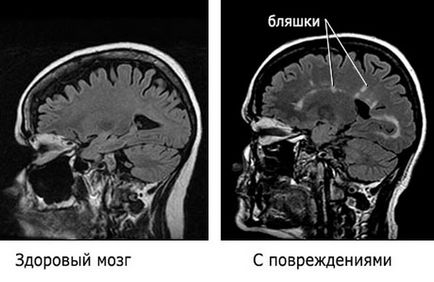

A betegség nagyon hosszú lappangási idő, hogy tarthat több héten át több éven át. Funkciók befolyásolja az immunrendszer sejtjei az agy, hogy gyorsan hozza a szomszédos sejtek és a károk nem észrevehető. Az első jelei a sclerosis multiplex észrevehetővé válik csak, ha az immunrendszer sérült Kolo 40 százaléka neuronokat. Alakult plakk tisztán látható a képen:

Ha úgy gondolja, egy személy a szklerózis multiplex csinálni mágneses rezonanciás képalkotás az agy, amely feltárja plakkok az agyban, ami már kialakult kötőszöveti.